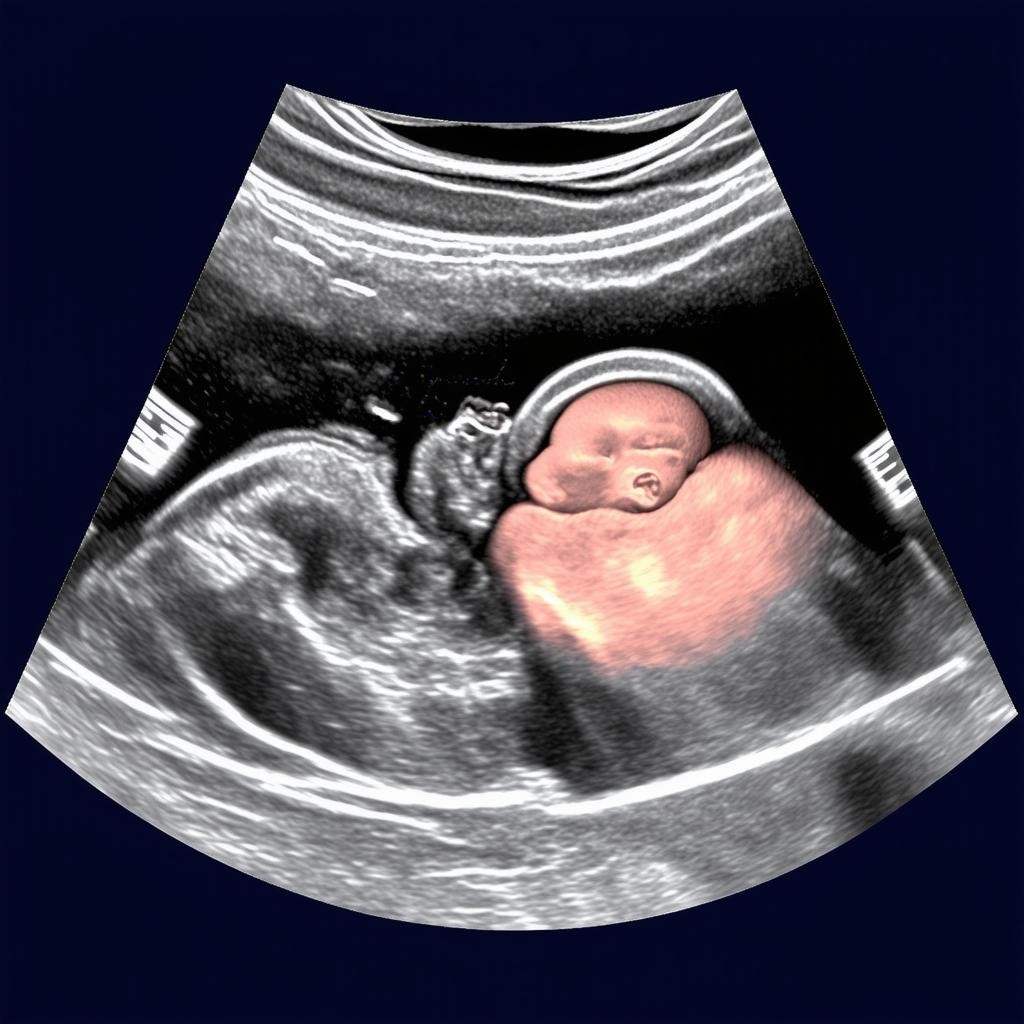

20 неделя беременности — это важный этап, когда проводится второе плановое ультразвуковое исследование (УЗИ). На этом сроке врач оценивает развитие плода, его анатомию, а также состояние плаценты и околоплодных вод. Это исследование помогает выявить возможные отклонения и убедиться, что беременность протекает нормально.

К 20 неделе беременности плод уже полностью сформирован, и врач может детально изучить его анатомию. Вот основные структуры, которые оцениваются во время УЗИ:

- Головной мозг: проверяется структура полушарий, мозжечка и желудочков.

- Сердце: оценивается частота сердцебиения (норма — 120-160 ударов в минуту) и строение камер.

- Позвоночник: проверяется целостность и отсутствие деформаций.

- Внутренние органы: почки, желудок, мочевой пузырь и кишечник должны быть хорошо видны.

- Конечности: врач проверяет наличие всех пальцев на руках и ногах.